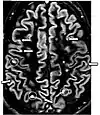

| Fluid-attenuated inversion recovery | FLAIR | Fluid suppression by setting an inversion time that nulls fluids | High signal in lacunar infarction, multiple sclerosis (MS) plaques, subarachnoid haemorrhage and meningitis (pictured).[24] | ![]() | |